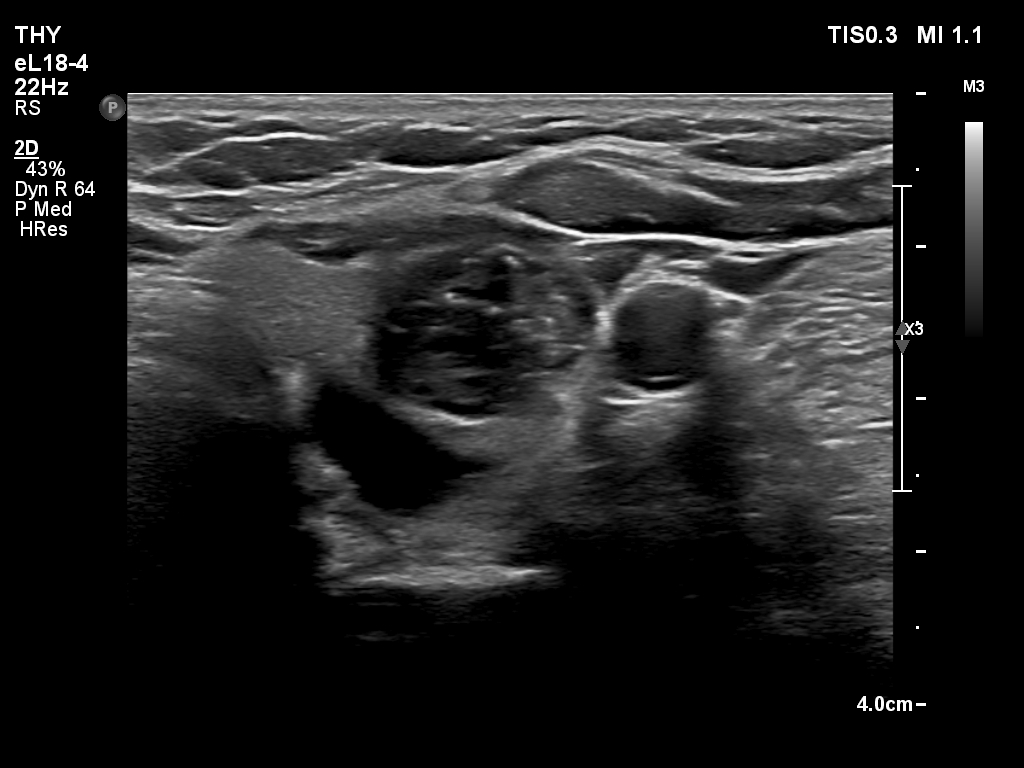

Ultrasonography. The thyroid was echonormal and had multiple nodules. There were cystic areas, an almost completely cystic nodule, and a dominantly solid nodule in the right lobe. The left lobe had three lesions. The upper solid lesion was the one we treated 16 years ago. The middle lesion was a dominantly solid while the lower one seemed to be a pure cyst. The dimensions of the nodule which has been treated with sclerotherapy were 10x11x13 mm (width, depth and length, respectively). There was a large cystic nodule in the upper pole of the left lobe. The lesion showed relatively large hyperechogenic granules. There were multiple enlarged lymph nodes lateral to the left lobe, two of largest were cystic.